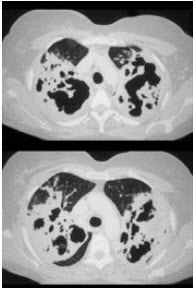

23、单项选择题

女,34岁,新月体肾炎患者,最近咳嗽咯血,第一次行胸片检查考虑为双下肺感染,抗感染治疗后无明显好转,症状加重,4天后复查并行CT检查如图,应考虑为()

A.肺泡蛋白沉着症

B.肺含铁血黄素沉着症

C.双下肺肺炎

D.肺出血肾炎综合征

E.韦格肉芽肿